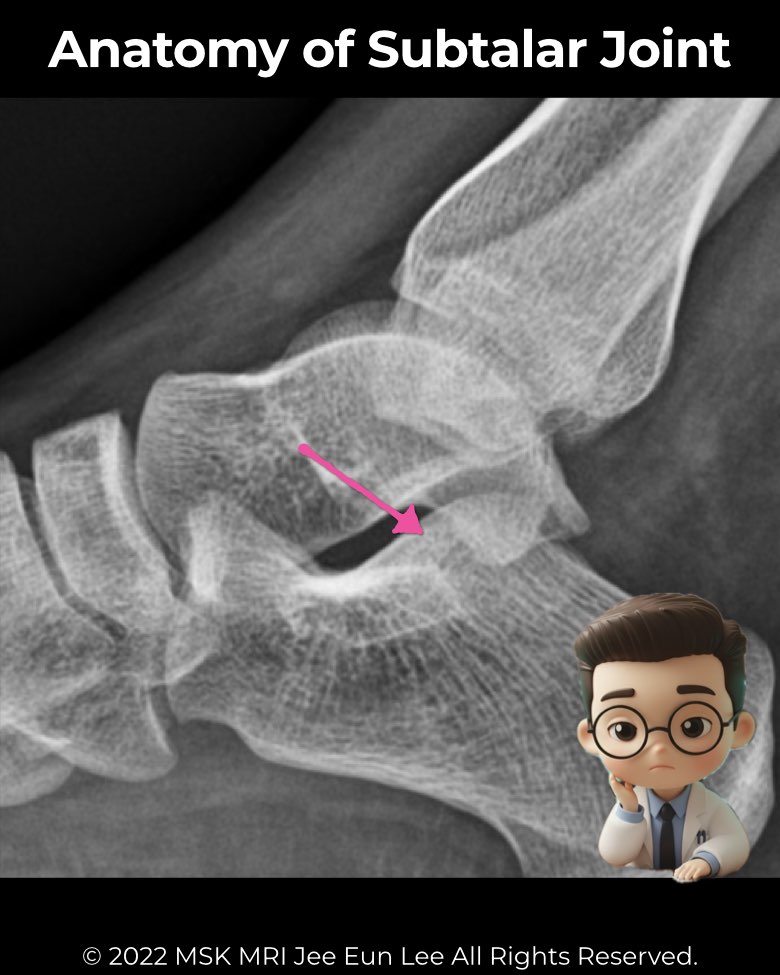

The subtalar joint (talocalcaneal joint) is vital for hindfoot stability and mobility.

- Posterior facet: largest, best seen on lateral radiographs and CT

- Anterior calcaneal process should not articulate with the navicular—if it does, think coalition

- Harris view: posterior and middle facets normally parallel (<20°)

- CT/MRI: gold standard for coalitions and subtle variants